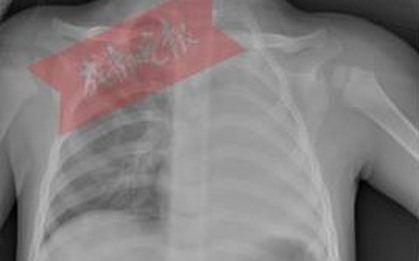

Phổi trái của bé trai 1 tuổi "biến mất", thủ phạm bất ngờ là món ăn thường xuất hiện vào dịp Tết, phụ huynh cần cảnh giác

Cha mẹ cần hết sức lưu tâm để tránh những nguy hiểm tiểm ẩn có thể xảy ra đối với con em mình.